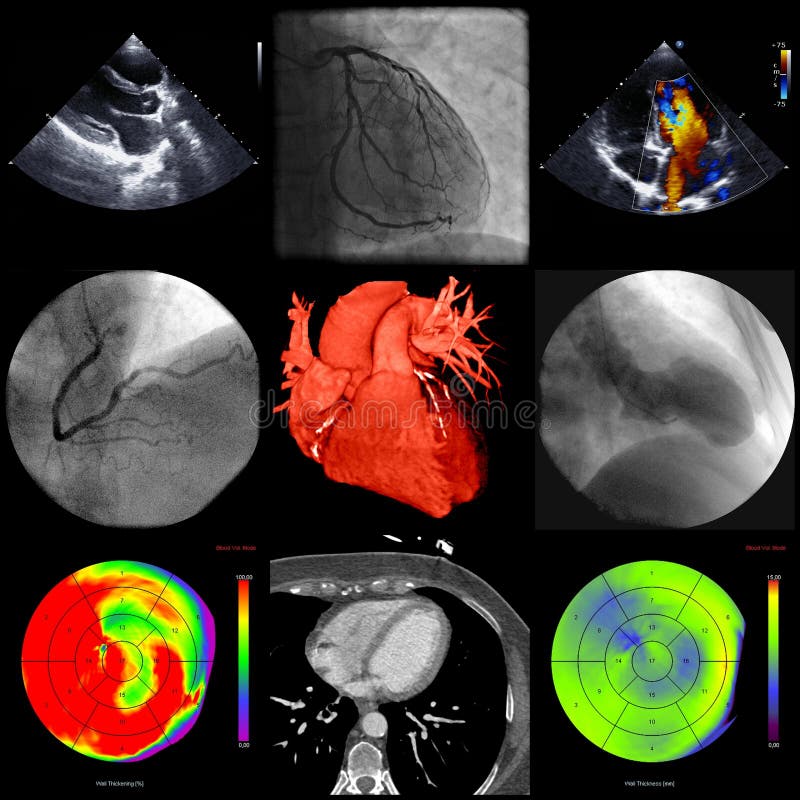

Various cardiac diagnostic tools are available to monitor and diagnose a variety of heart conditions. They are modern technologies that help us figure out the condition of the heart non-invasively. It is important to select the appropriate imaging modality based on clinical presentation, pre-test probability, hemodynamic status, and resource availability. Four cornerstone modalities are

Each technology works differently and may help identify specific cardiac structures and functions.

This technology uses the use of echoes from the waves produced to detect the structure and function of the heart. It includes transthoracic (TTE), transesophageal (TEE), and stress echocardiography.

This technique provides real-time visuals of the cardiac function. It is the first-line imaging modality in assessing the heart morphology and pumping mechanism. It shows a clear view of the valvular anatomy and visualizes its abnormality.

Cardiac CT provides a clear visual of the intricate soft tissue components of the heart by providing cross-sectional views of selected segments. It provides high-resolution anatomical imaging, especially of the coronary arteries. It includes coronary CT angiography (CCTA) and calcium scoring.

It is preferred in cases of stable heart diseases rather than hemodynamics or myocardial tissue identification.

Provides high-resolution structural, functional, and tissue characterization without any ionizing radiation.

Cardiac MRI is the reference standard for myocardial tissue characterization and cardiomyopathy workup. It is often used when echo findings are inconclusive or when detailed myocardial assessment is required.

ECG, echocardiography, cardiac CT, and cardiac MRI are not competing modalities but complementary tools in cardiovascular diagnostics.

Optimal utilization requires alignment with clinical presentation, diagnostic yield, patient comorbidities, and guideline recommendations. A multimodality approach, when indicated, enhances diagnostic precision and patient outcomes.